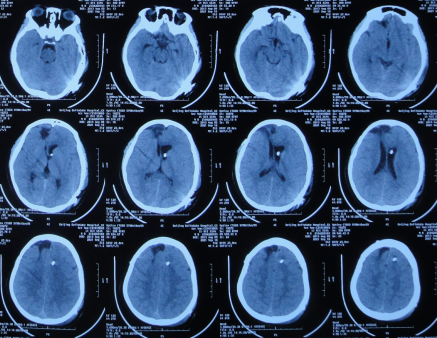

女朋友从楼梯上摔下不小心碰到后脑,拍ct医生说先观察几天,请能看懂的

右侧枕叶脑后见大片状稍长t1t2信号头晕眼花记忆力减退